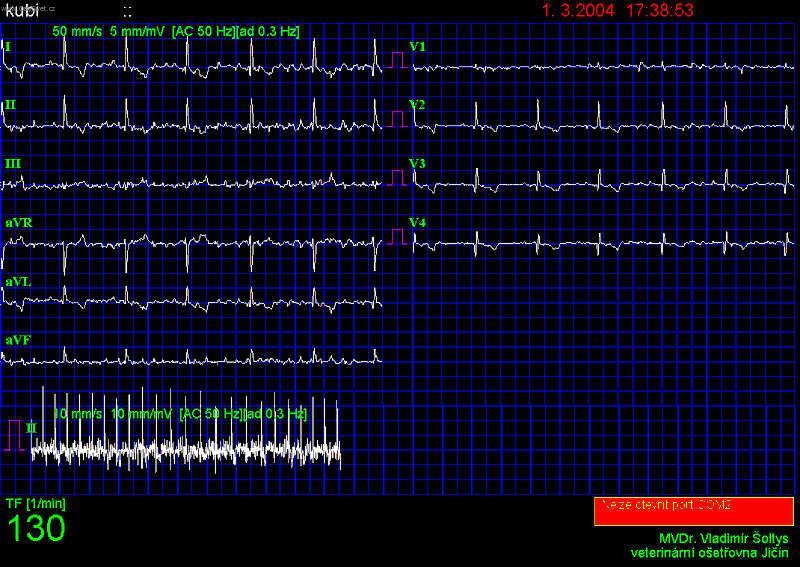

Fibrilace síní